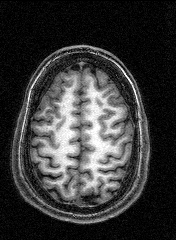

The last session involved several MRI and fMRI scans while completing tasks in the noisy environment of the scanner. Thanks to a friend who worked at the Institute, I was able to secure a copy of the raw data and an application to turn it into images, some of which are displayed here.

The images to the right are virtual 'slices', taken horizontally, starting from the top and working down. Cerebrospinal fluid is dark, the white matter appears light.

Medical images such as these are easy to come by on the internet, but having images of your own brain brings a humbling perspective.